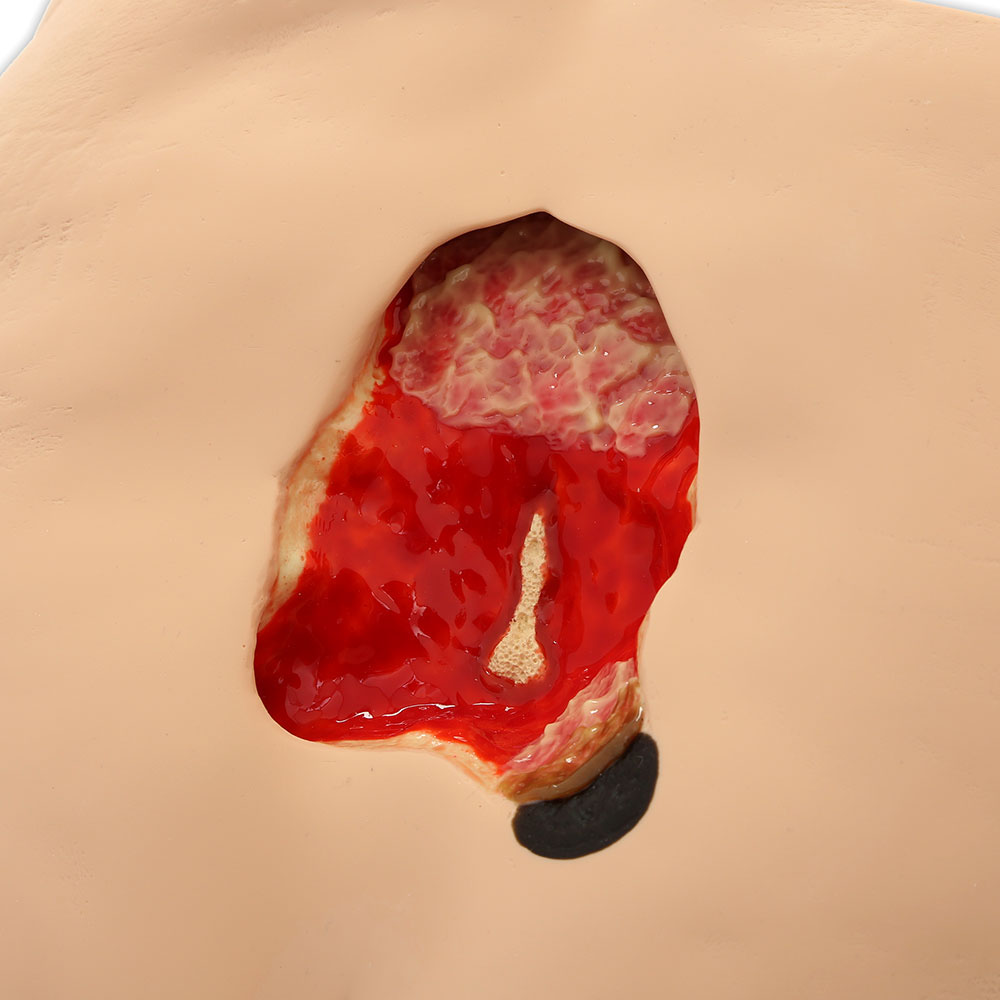

- Wound care simulation model displays the following pressure injuries:

- Stage 3 with undermining

- Tunneling

- Subcutaneous fat

- Slough

- Deep Stage 4 with exposed bone with osteomyelitis, undermining, tunneling, subcutaneous fat, eschar and slough

- Great care has been taken to hand paint each wound just as you would see it on a patient for the most life-like patient training scenario

- The Stage 3 and Stage 4 are positioned so that a “bridging” dressing for use with a vacuum-assisted closure and negative pressure wound therapy devices can be demonstrated and practiced